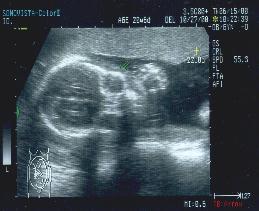

妊娠22週の胎児